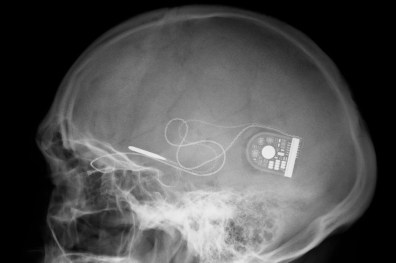

Hard on the heels of their proposed BRAIN initiative – a collaborative research initiative to map the activity of every neuron in the human brain – DARPA has announced a bold new program to develop tiny electronic implants that will be able to interface directly with the human nervous system to control and regulate many different diseases and chronic conditions, such as arthritis, PTSD, Crohn’s disease, and depression.

The program, called ElectRx (pronounced ‘electrics’), ultimately aims to replace medication with “closed-loop” neural implants which monitor the state of your health and then provide the necessary nerve stimulation to keep your organs and biological systems functioning properly. The work is primarily being carried out with US soldiers and veterans in mind, but the technology will certainly percolate down to civilians as well.

The ElectRx program will focus the relatively new area of medical therapies called neuromodulation, which seeks to modulate the nervous system to improve neurological problem. Notable examples of this are cochlear implants which restore hearing by modulating your brain’s auditory nerve system, and deep brain stimulation (DBS) which is apparently capable of curing/regulating conditions like depression and Parkinson’s by overriding erroneous neural spikes.

So far, these implants have been fairly large, which makes implantation fairly invasive and risky. Most state-of-the-art implants also lack precision, with most placing the stimulating electrodes in roughly the right area, but which are unable to target a specific bundles of nerves. With ElectRx, DARPA wants to miniaturize these neuromodulation implants so that they’re the same size as a nerve fiber.

This way they can be implanted with a minimally invasive procedure (through a needle) and attached to specific nerve fibers, for very precise stimulation. While these implants can’t regulate every condition or replace every medication (yet), they could be very effective at mitigating a large number of conditions. A large number of conditions are caused by the nervous system misfiring, like inflammatory diseases, brain and mental health disorders.